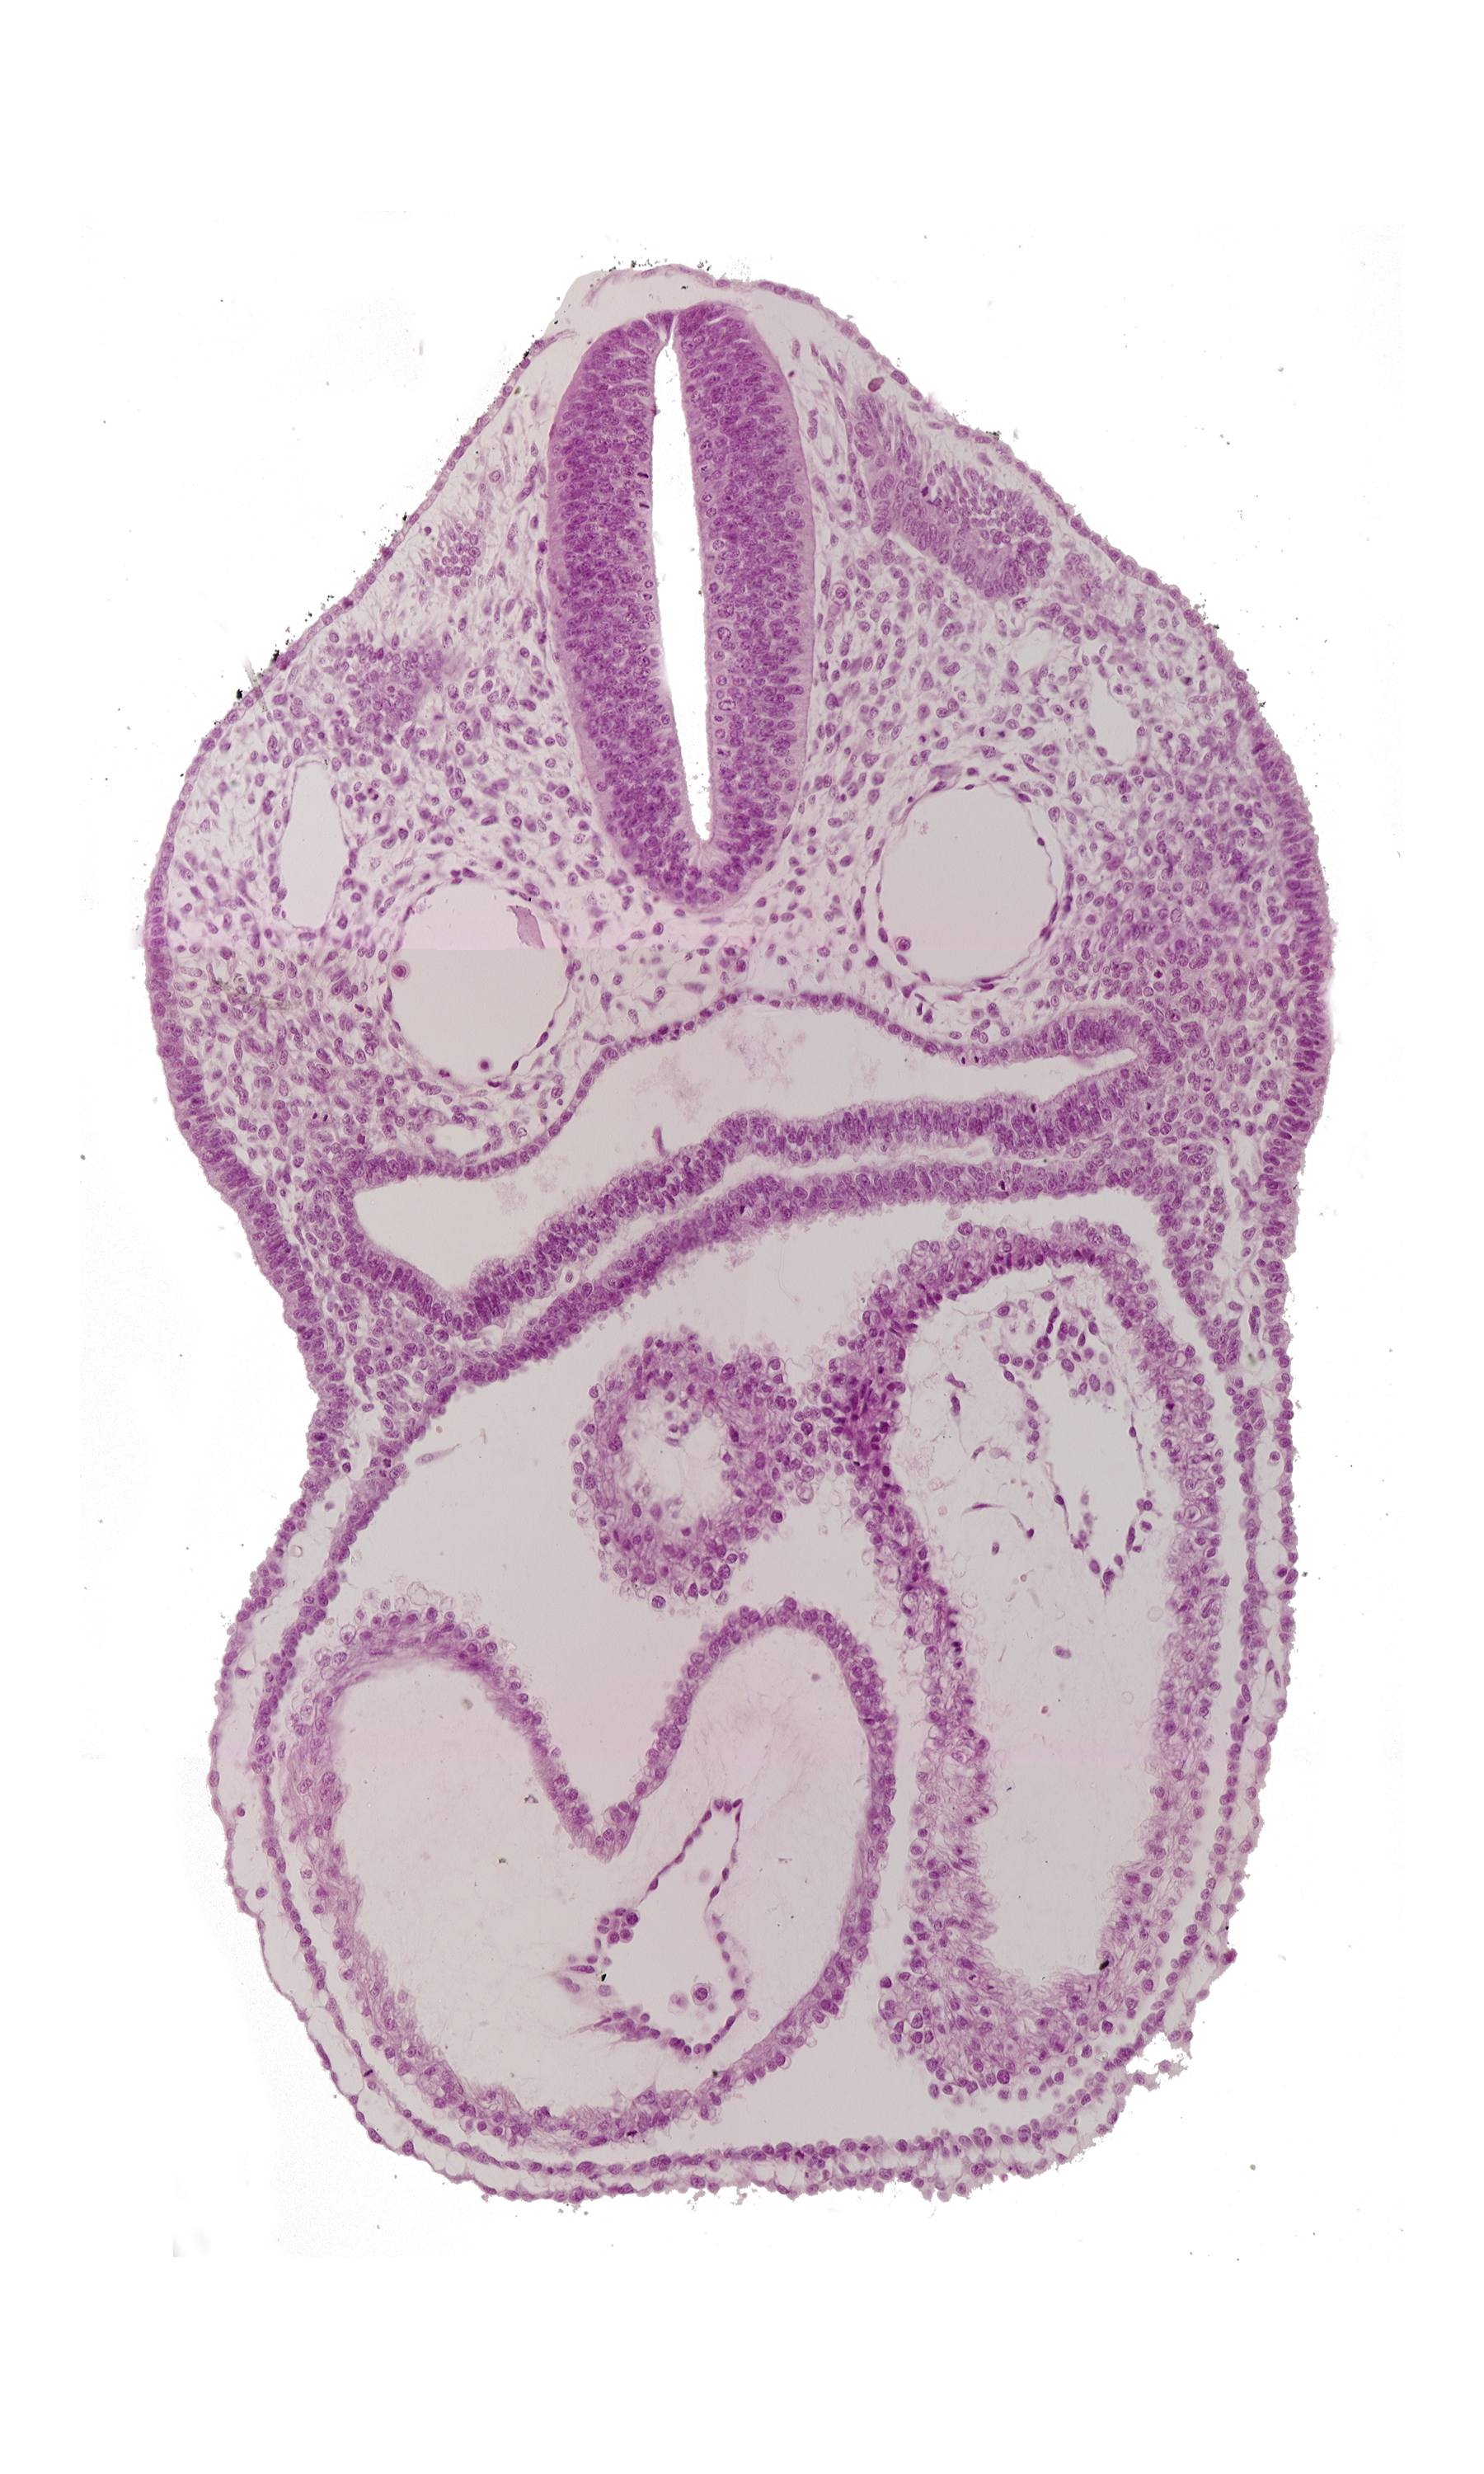

Carnegie Embryo #8943 | Location: 03-05-03

Keywords: atrioventricular canal, cardiac jelly, conus cordis, dermatomyotome 3 (O-3) , dorsal aorta, ectodermal ring, endocardium, epimyocardium, left atrium, left ventricle, notochord, pericardial cavity, pharyngeal pouch 4, pharynx, precardinal vein, rhombencephalon (Rh. D), right atrium, sclerotome, truncus arteriosus

Source: The Virtual Human Embryo.